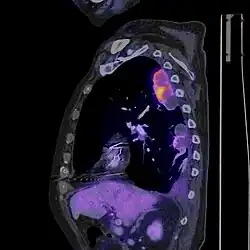

PET/CT je diagnostická zobrazovací metoda spojující vyšetření počítačovou tomografií (CT) a pozitron emisní tomografií (PET). Získané obrazy obsahují jak poměrně podrobnou informaci o anatomické stavbě, tak i informaci o metabolické aktivitě tkání.